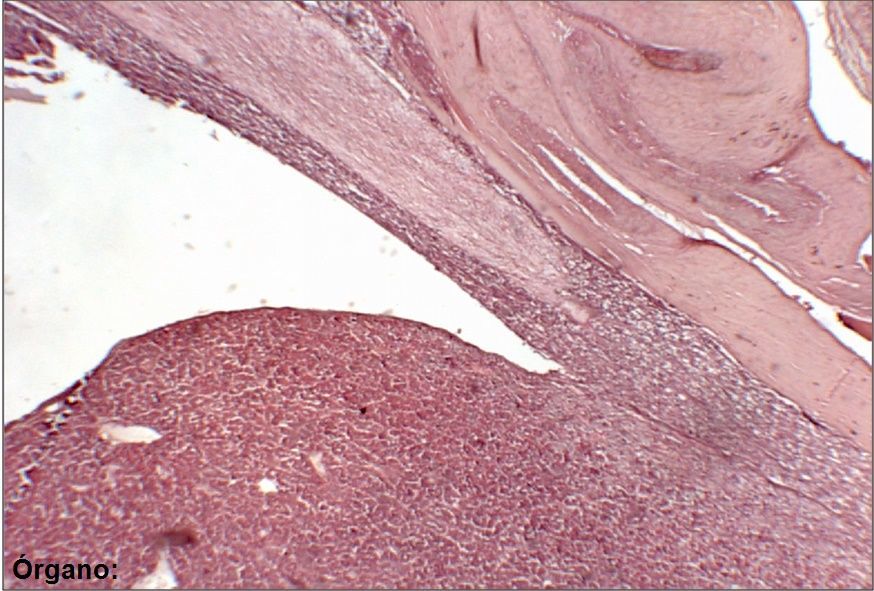

Question

Escriba el nombre de las estructuras marcadas (dos palabras por cada estructura) y del órgano (abajo a la izquierda). Nota: tenga en cuenta los acentos y las faltas de ortografía.

Answer

• Sustancia gris

• Sustancia blanca

• Canal ependimario

• Médula espinal